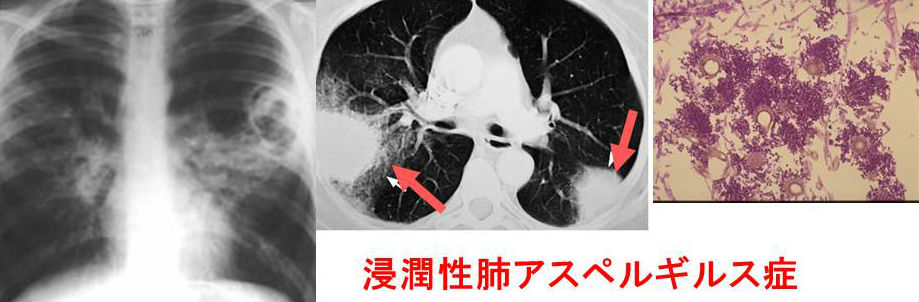

侵襲性肺アスペルギルス症

アスペルギルスは様々な肺疾患の原因になります。胸X-pでは甲状腺癌肺転移と鑑別できなくても肺CTで鑑別できます。

アスペルギルスは糸状真菌で、糖尿病や悪性腫瘍など免疫不全患者に侵襲性肺アスペルギルス症をおこします。

真菌感染特有の血清ガラクトマンナン抗原(アスペルギルスの細胞壁を構成する蛋白の一つ)やβ(ベータ)‐Dグルカンが上昇、出血性梗塞と周囲の肺胞内出血が特徴です。

甲状腺にも血行性感染し、急性化膿性甲状腺炎の一つアスペルギルス甲状腺炎を起こします。

空洞内菌球(アスペルギローマ)

免疫低下していない状態では、結核など既存の空洞に感染して、菌球(アスペルギローマ)を複数形成します。